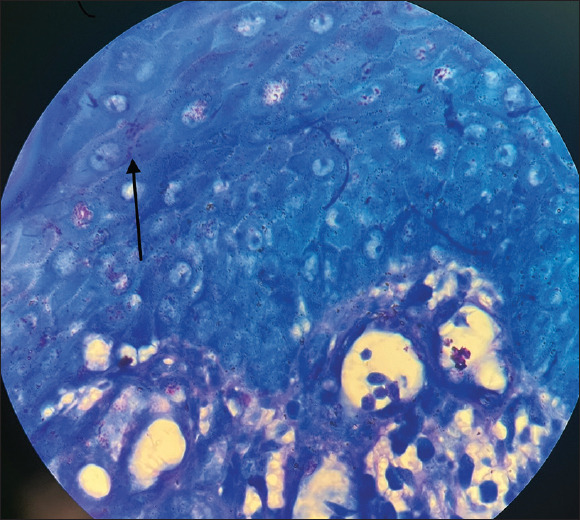

Donovanosis is a chronic granulomatous ulcerative sexually transmitted infection caused by Klebsiella (Calymmatobacterium) granulomatis. A 39-year-old female patient with underlying HIV infection presented to the department of dermatology outpatient department with a painless ulcer over the left labia majora for 3 months. Histopathological examination revealed histiocyte which contains granular material resembling coccobacilli and Giemsa staining was positive for Donovan bodies. She was treated with doxycycline 100 mg twice daily and azithromycin 1 g once weekly for 3 weeks and further azithromycin 1 g weekly for the next 9 weeks till complete healing of the lesion. Due to the rarity of this condition in our region, we present this case of donovanosis in an HIV-positive female patient.